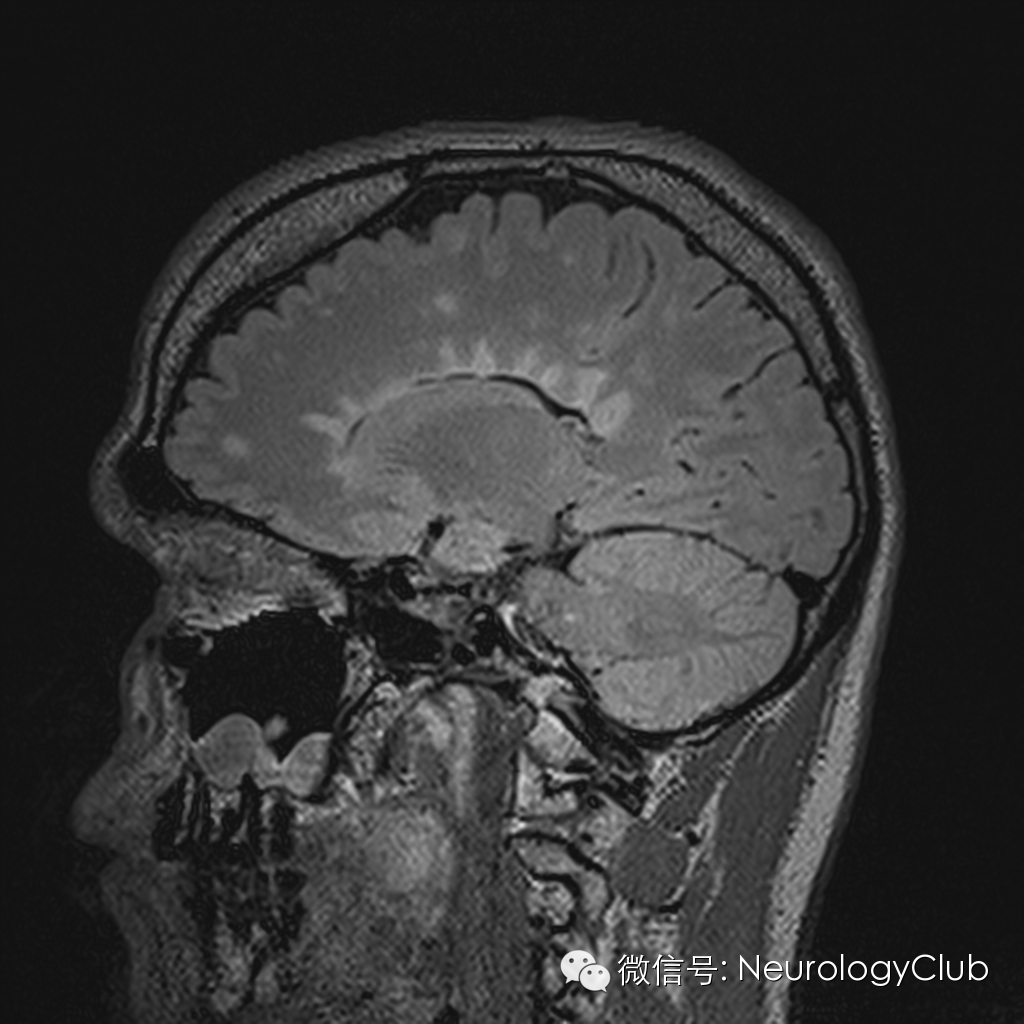

Dawson手指征(Dawson finger sign)

Dawson手指征(Dawson finger sign)为头颅MRI上,T2WI/FLAIR 显示侧脑室旁白质内多发条状、卵圆形、指状或火焰样高信号病灶,其长轴垂直于侧脑室边缘(矢状位也可见病灶累及胼胝体),类似于手掌五指张开的表现。这种征象在矢状位、轴位、冠状位均可以观察到。

(图片取自网络)